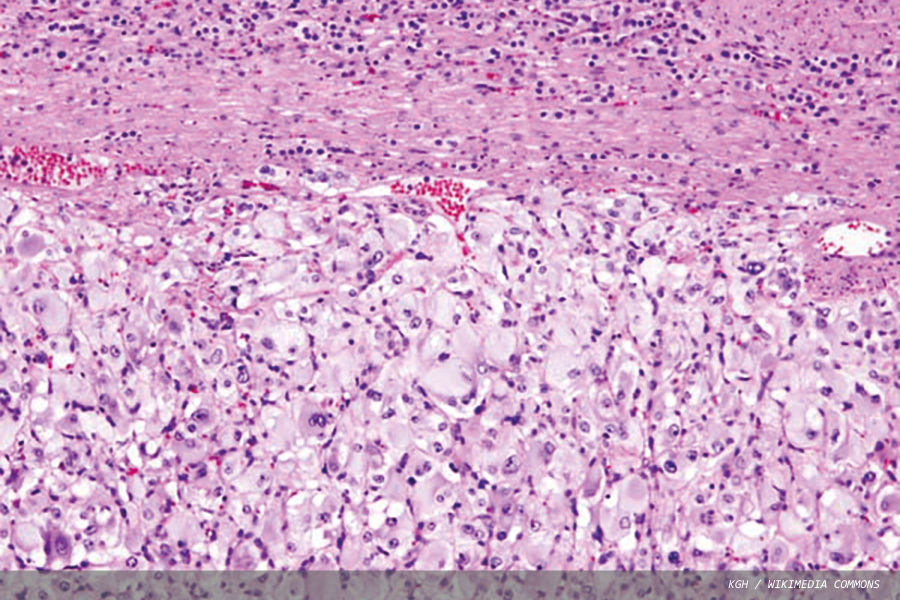

Phaeochromocytomas and paragangliomas develop from neuroendocrine chromaffin cells. Tumours developing from such cells are called phaeochromocytomas if found in the medulla of the adrenal gland, or paragangliomas if growing elsewhere in the body. Here, Pathology in Practice Science Editor Brian Nation looks at a selection of current research in the literature.

Phaeochromocytoma is a rare neuroendocrine tumour that develops from chromaffin cells in the adrenal medulla and is characterised by the excessive production of catecholamines and their metabolites. Diagnostic confirmation is performed by detecting elevated levels of catecholamines and/or their metabolites in plasma or 24-h urine.